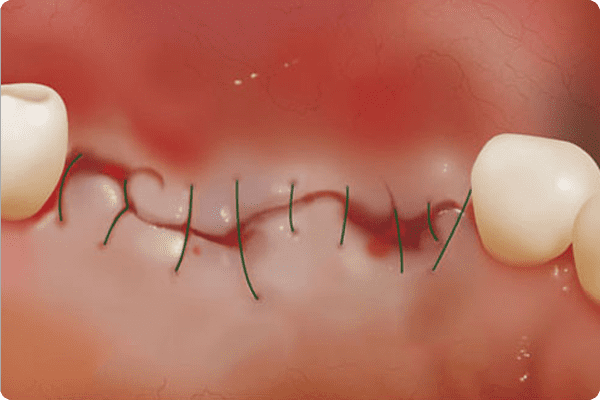

절개시술

잇몸 절개로 붓기·출혈 발생

컴퓨터 분석

임플란트수술 당일 붓기·출혈이 거의 없는 모습

아플까봐 걱정돼요기존의 임플란트 수술의 경우 잇몸을 절개한 후

눈으로 직접 뼈 상태를 파악했기 때문에

시술 시간이 다소 오래 걸리며 경우에 따라

출혈이 심하거나 잇몸이 붓는 등 통증이 발생했습니다.

하지만 컴퓨터 분석 임플란트는 잇몸뼈 상태를

파악하기 위해 잇몸을 크게 절개할 필요가 없습니다.

수술 유도장치를 통해 작은 구멍을 낸 후

바로 임플란트를 심을 수 있어 출혈과 붓기,

통증이 적고 수술 후 빠른 회복을 기대할 수 있습니다.